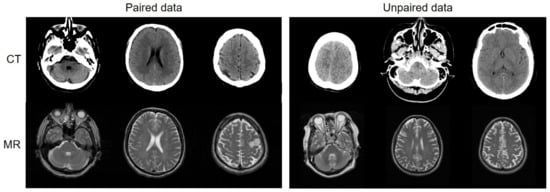

Most medical institutions have considerable unpaired data that were scanned for different purposes and different radiotherapy treatments. Being able to use the unpaired data would increase the amount of available training data exponentially and alleviate many of the constraints of the existing deep learning-based synthetic systems (Figure 1). Unlike the paired-data-based methods in [16,19,20,22], Wolterink et al. [24] used a CycleGAN model [25], which is an image-to-image translation that uses unpaired images to synthesize CT images from MR images. In an unpaired GAN paradigm, it is desirable for the synthesized image to look real and be paired up with an input image in a meaningful way. Therefore, cycle-consistency loss is enforced to translate the synthesized image back to the original image domain and minimize the difference between the input and the reconstructed image as a regularization. Because of a large amount of unpaired data, the synthesized images are more realistic than the results from the paired training methods. However, compared to the voxel-wise loss of the paired data, the cycle-consistent loss still has certain limitations in correctly estimating the contextual information of soft tissues and blood vessels. Therefore, in our study, the objective function of the MR-GAN includes voxel-wise loss and cycle-consistent loss to benefit from the stable optimization of supervised learning and a massive dataset of unsupervised learning.

Figure 1. (Left): Deep networks train with paired data, which include CT and MR slices taken from the same patient at the same anatomical location. Paired data must be intentionally collected and aligned, which imposes difficulty. However, paired data provide network regression constraints that are far more correct. (Right): Deep networks train with unpaired data, which include CT and MR slices taken from different patients at different anatomical locations. There is a considerable amount of unpaired data available.